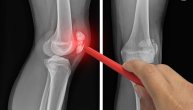

Lekari razlikuju nekoliko različitih načina na koje lakat može da boli Foto: Shutterstock

Lakat je zglob, koji se formira na mestu gde se spajaju tri kosti - kost nadlaktice ili humerus, i lakatna kost i radijus - dve kosti koje čine podlakticu. Svaka kost ima hrskavicu na kraju, što im pomaže da klize jedna o drugu i apsorbuju udarce. Pričvršćene su čvrstim tkivima zvanim ligamenti, a tetive povezuju kosti sa mišićima kako bi bilo moguće da se ruka pomera na različite načine. Ako se bilo šta desi nekom od ovih delova, da ne pominjemo nerve i krvne sudove oko njih, to može da bude uzrok bola.

• Artritis: Mnogi tipovi artritisa mogu da utiču na lakat, ali glavni su reumatoidni artritis i osteoartritis. Reumatoidni artritis je najčešći tip artritisa u laktu. Kada čovem ima reumatoidni artritis imuni sistem napada zdravo tkivo tela i izaziva oticanje u zglobovima. Osteoartritis dobija se kada se hrskavica lakta s vremenom potroši, ošteti, što znači da dolazi do trenja i kosti počinji da se trljaju jedna uz drugu i izazivaju bol i ukočenost.